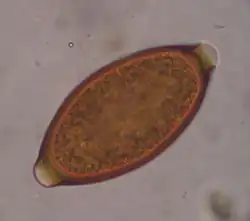

Trichuris vulpis is a whipworm that lives in the large intestine of canines in its adult stages. Out of different types of worms, Trichuris vulpis is one of the smaller worms with a size ranging from 30–50 mm in length. As the name suggests, the worm has a whip-like shape with distinct features including a small, narrow anterior head, which is the digestive part of the worm, and a larger posterior tail, which is the reproductive part of the worm. Eggs from T. vulpis are oval shaped with bipolar plugs and contain a thick outer shell. Their sizes range from 72–90 μm in length and 32–40 μm in width.[1] Because of their thick outer shell, T. vulpis eggs are very resistant to environmental extremes such as freezing or hot temperatures, thus allowing for their long viability in the outside world.[2]

Egg of T. vulpis

The life cycle of Trichuris vulpis begins with the adult whipworms living in the large intestines of dogs. T. vulpis lay many eggs in the large intestine and are released in the feces into the outside environment. When eggs are released into the outside environment, these unembryonated eggs are able to form embryos in the soil in about 2–4 weeks, at which point they become infective when ingested by the new host. An infective larva develops within the egg before it is even ingested by the new host.[3]

Infection of this parasite can be confirmed with detection of eggs in the canine's feces. Adult T. vulpis females can produce more than 2,000 eggs per day. These eggs can be detected in the canine's feces by the fecal flotation method.[14] This method utilizes the differences of specific gravity of eggs, fecal debris, and the flotation solution.[15] Although these eggs are dense, the use of proper fecal flotation technique using a sugar solution and centrifugation can increase the chances of identifying these eggs in a fecal sample.[16] Multiple fecal samples may need to be tested as the eggs may be shed periodically.[17]